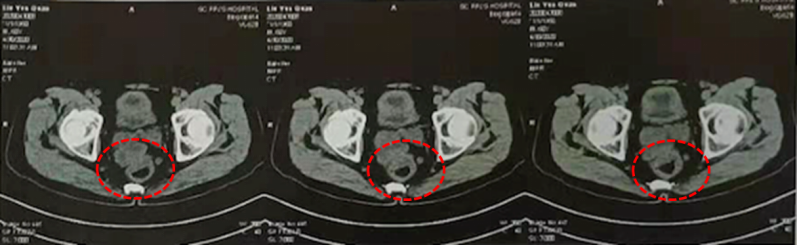

(1)2020-4-11 全腹部CT增强扫描:直肠周围淋巴结较前增多、增大,局部直肠壁肿厚,右前方见团块状软组织密度影(约3.9cm*2.8cm)。

(2)2020-4-25 盆腔增强MRI:直肠中上段占位,考虑肿瘤性病变,累及肠系膜筋膜及腹膜反折,直肠周围系膜、双侧盆壁及双侧腹股沟区多发淋巴结,部分淋巴结转移可能。